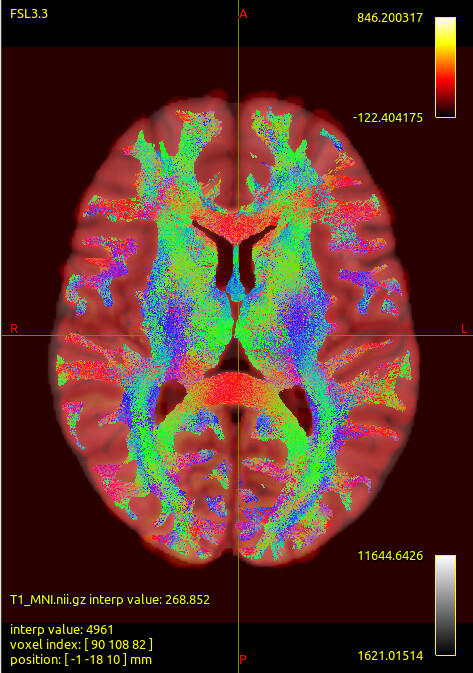

We noticed that the tck files already warped to MNI space are misaligned with the standard template in some sulcal and gyral regions. However, we also checked the registration between the T1 image and MNI space — even the T1 image warped to MNI space fails to align with the sulci and gyri of the MNI template. Nevertheless, the tck files in standard space show better alignment with the T1 image in MNI space. Can this be considered a good warping result? Figures are as follows.